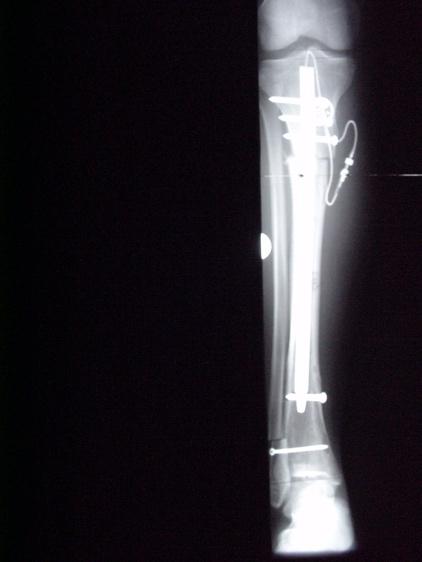

Um die Möglichkeiten der Kallusdistraktion zu nutzen, ohne die Nachteile der externen Fixateure in Kauf nehmen zu müssen, wurden seit den 1980er Jahren voll implantierbare Distraktionsmarknägel entwickelt. Konventionelle Marknägel aus Stahl oder Titan werden

schon seit über 50 Jahren in der Behandlung von Knochenbrüchen verwendet. Auf solchen Marknägeln basieren alle heute auf dem Weltmarkt erhältlichen Distraktionsmarknägel. Diese besitzen ein ausgeklügeltes Innenleben, das ihnen die Distraktion erlaubt.

Fitbone II® im Unterschenkel Albizzia® im Oberschenkel BetzboneÒ im Oberschenkel